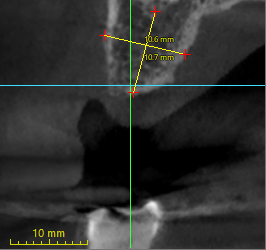

Hi all, Im trying to place a single unit #13. Due to boneloss, it looks like the buccal side is longer than the palatal side. If I were to place #13 completely submerged, 1mm subcrestal on the lingual side, it looks like it would be 2.2mm subcrestal on the buccal side. Should I shave down 1mm of the buccal bone to make it more even?

If so, do…